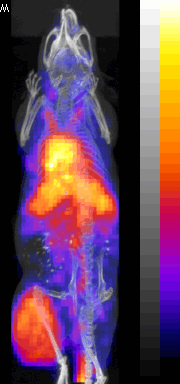

SPECT/CT Images

111In labeled oligomer |

188Re labeled oligomer |

99mTc labeled oligomer |

99mTc labeled peptide |

SPECT/CT fusion of 99mTc-MDP Bone Scan